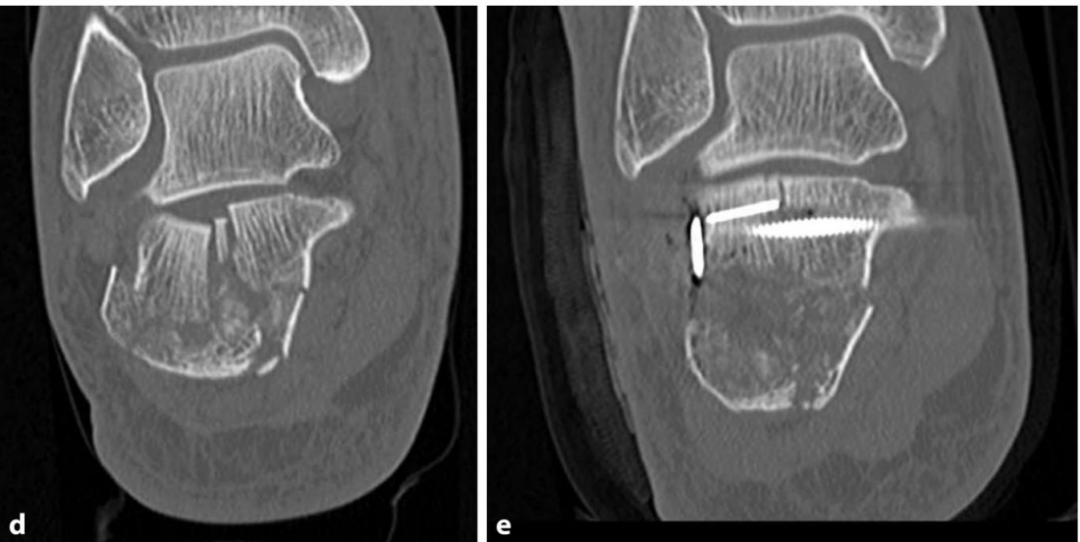

随后,将关节面骨块由内向外逐步贴合恒定骨块进行复位重建,利用细骨撬检查骨块的高度、关节面的对合情况及骨折块的旋转角度是否正常。

采用 1.4mm 或 1.6mm 克氏针进行临时固定,通过侧位透视与Broden位透视检查复位效果,亦可根据需要采用关节镜直接检查关节面的对合情况,在后足内翻应力下可获得充足的关节显露视野。

步骤 4:内固定稳定

根据关节内骨折块的大小,选用 2.0~3.5mm 拉力螺钉进行固定;最终固定主要采用外侧锁定钢板内固定,微创入路手术中,亦可使用大骨折块螺钉将跟骨结节骨块固定于关节骨块或跟骨前突。